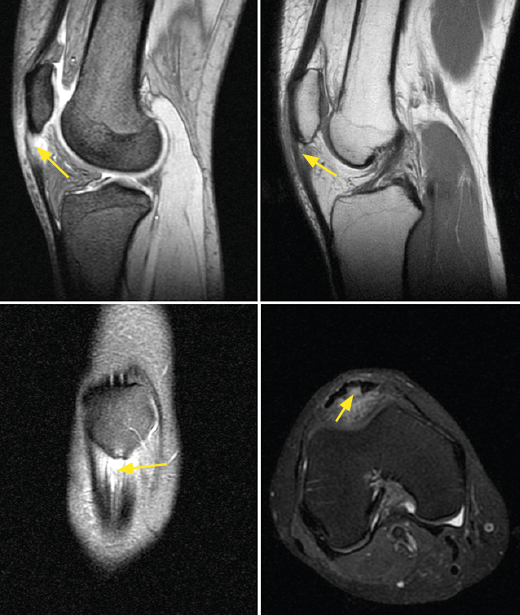

It has been demonstrated that both colour Doppler ultrasound (CD-US) (Figure 2) and MRI (Figure 3) are useful tools for confirming the diagnosis and can orientate treatment(10). Over the last two decades, ultrasound tissue characterization (UTC) has been developed with the purpose of obtaining even more information than conventional ultrasound. Indeed, the technique has become so important that some authors consider that UTC could be the most important development in medical US imaging since the introduction of Doppler ultrasound(13). Ultrasound tissue characterization is an imaging technique specifically designed for application to tendons. It is based on a colour scale that allows us to determine the degree of elasticity of the tendon tissue, and is able to measure small changes in tendon structure (e.g., as in evaluating the presence of tissue degeneration or fibrosis) - allowing us to establish an early diagnosis that can limit chronification of the process. The technique also has therapeutic applications as a tool for monitoring and guiding ongoing treatments, even after surgical repair, or for measuring the time for returning to physical activity (particularly in top athletes)(14,15).

Figure 3. Magnetic resonance imaging (MRI) view of a patient with long-evolving patellar tendinopathy. Note thickening of the tendon in the sagittal and coronal views, as well as internal destructuring of the collagen fibers (marked by arrows).